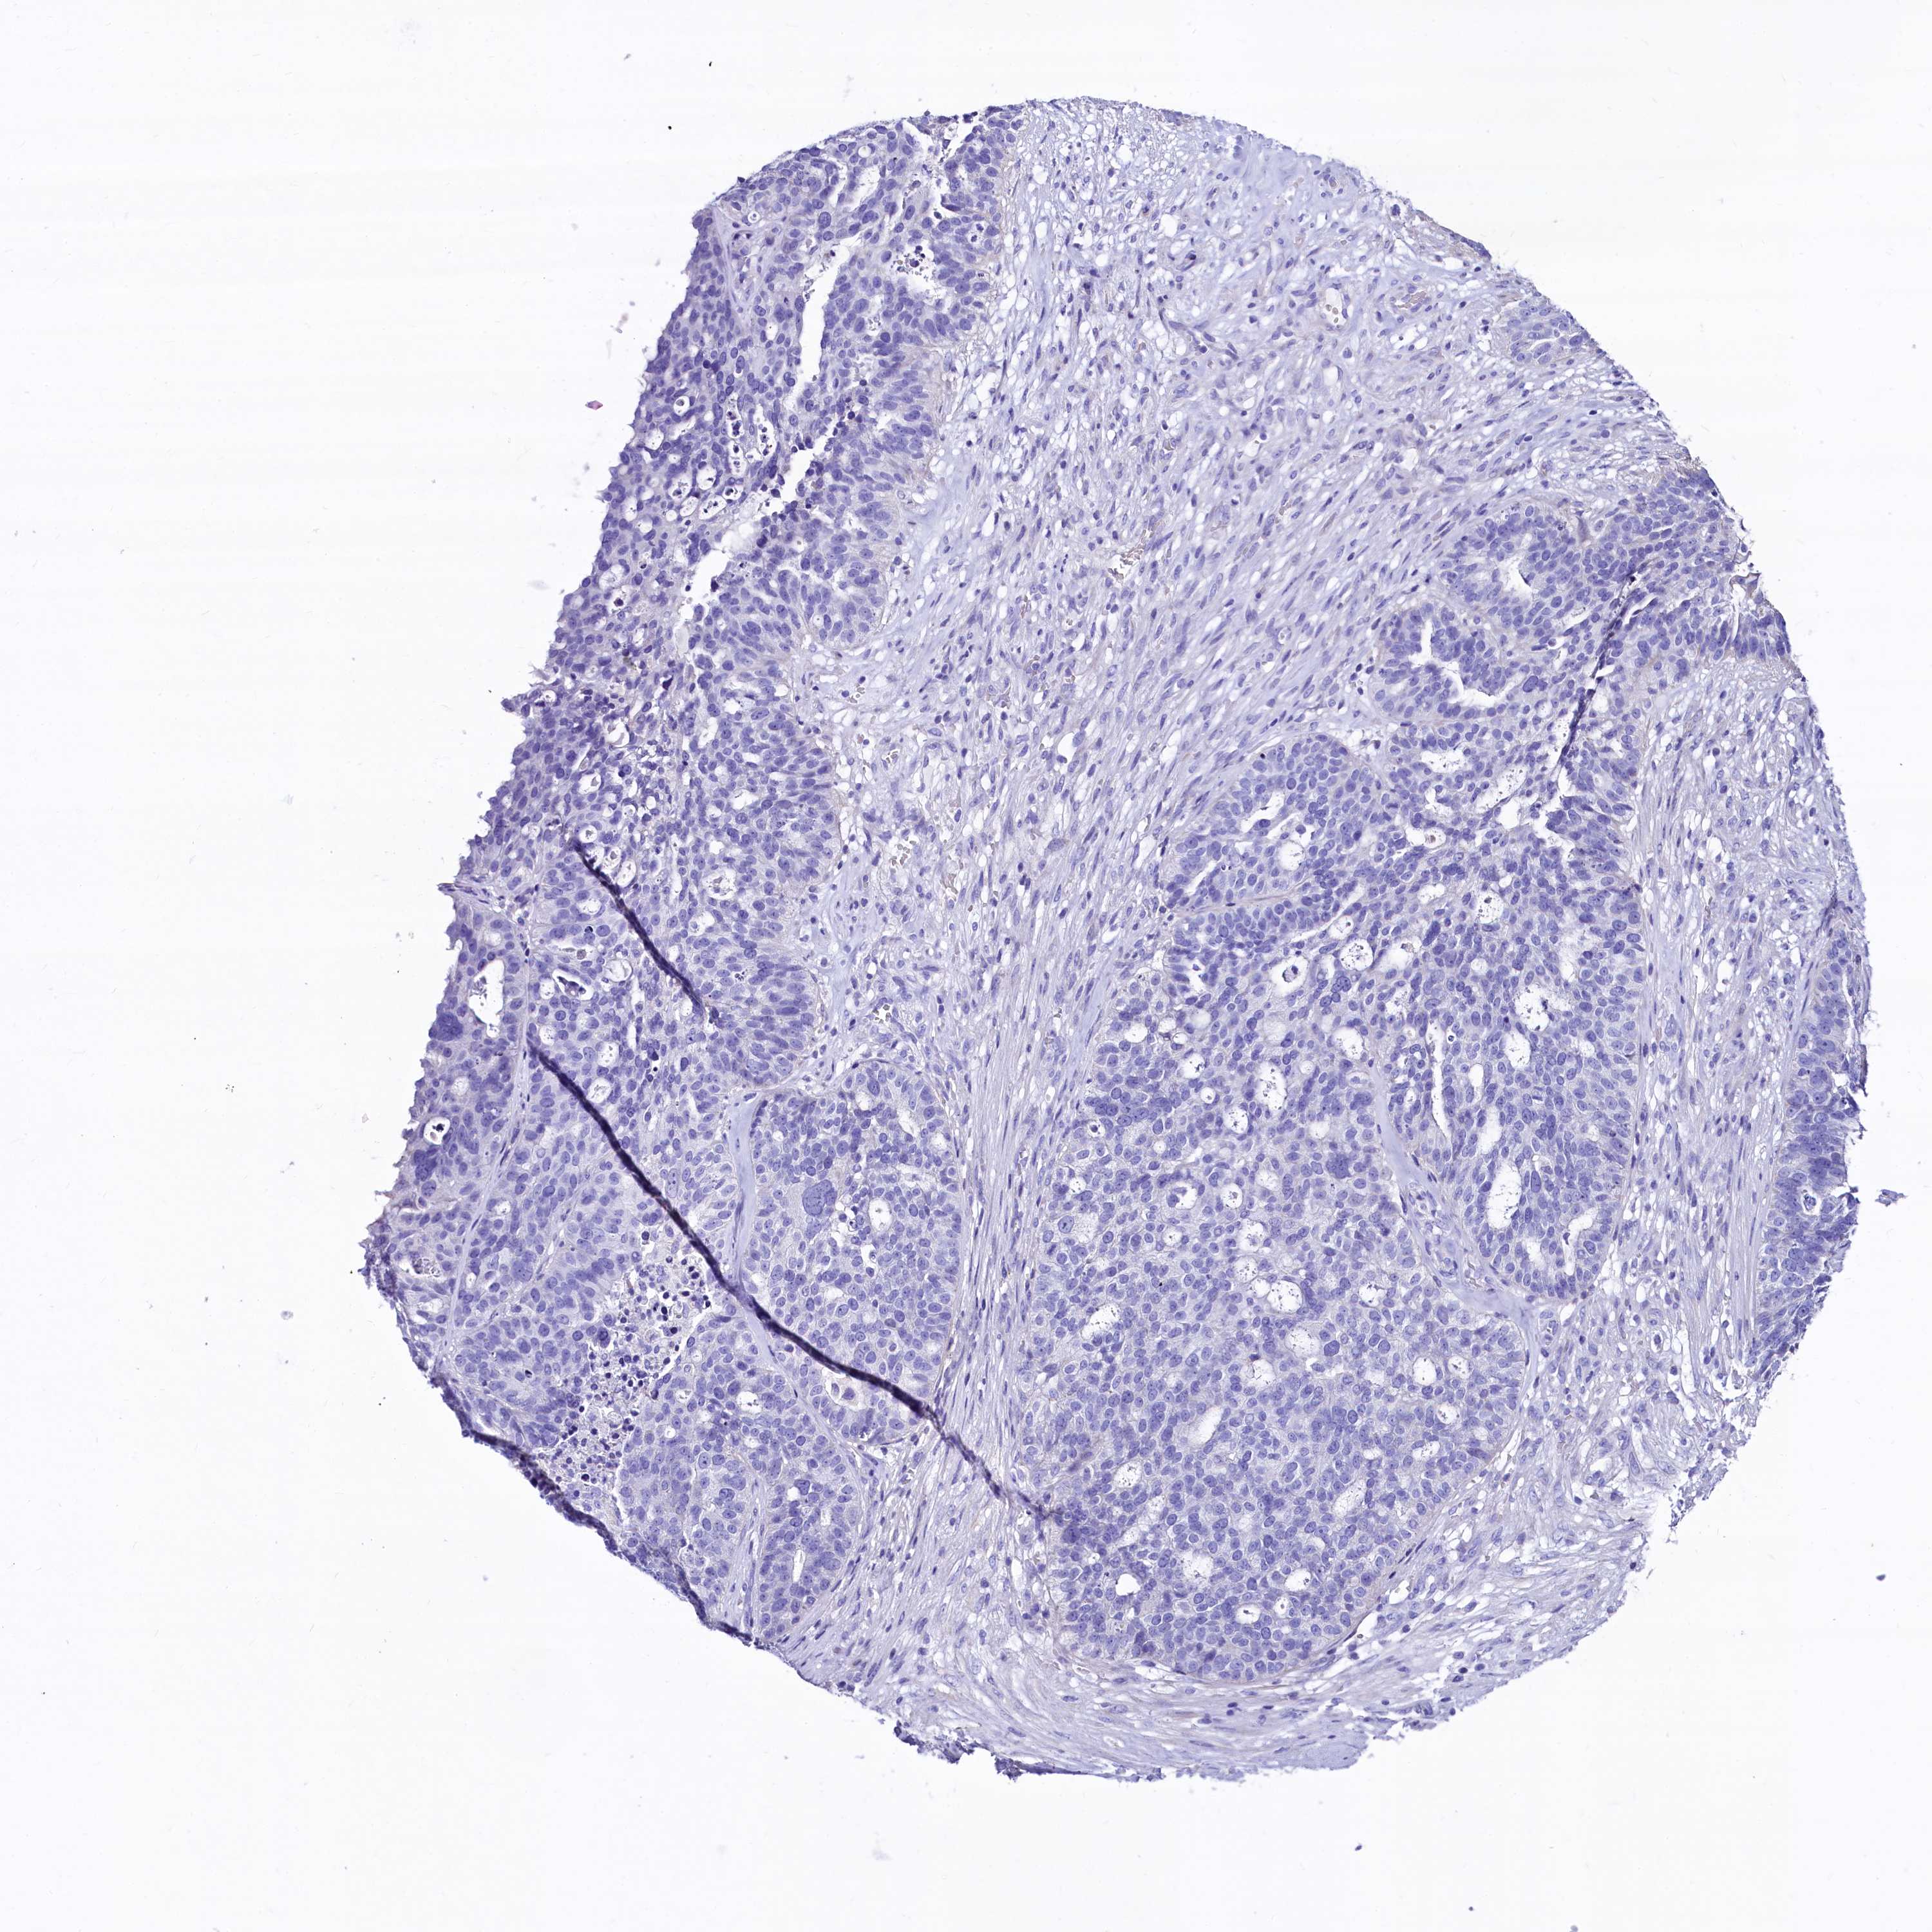

OVARIAN CANCER - Protein expressioni

A mouse-over function shows sample information and annotation data. Click on an image to view it in a full screen mode. Samples can be filtered based on level of antibody staining by selecting one or several of the following categories: high, medium, low and not detected. The assay and annotation is described here.

Note that samples used for immunohistochemistry by the Human Protein Atlas do not correspond to samples in the TCGA dataset.

Antibody stainingi

Antibody staining in the annotated cell types in the current human tissue is reported as not detected, low, medium, or high, based on conventional immunohistochemistry profiling in selected tissues. This score is based on the combination of the staining intensity and fraction of stained cells.

Each image is clickable and will lead to virtual microscopy that enables deeper exploration of all samples and also displays staining intensity scores, fraction scores and subcellular localization as well as patient and tissue information for each sample.

Antibody HPA041301

Antibody HPA044239

Staining

High

Medium

Low

Not detected

Intensity

Strong

Moderate

Weak

Negative

Quantity

>75%

75%-25%

<25%

None

Location

Nuclear

Cytoplasmic/membranous

Cytoplasmic/membranous,nuclear

Cystadenocarcinoma, serous, NOS

Carcinoma, endometroid

Cystadenocarcinoma, mucinous, NOS

Carcinoma, NOS